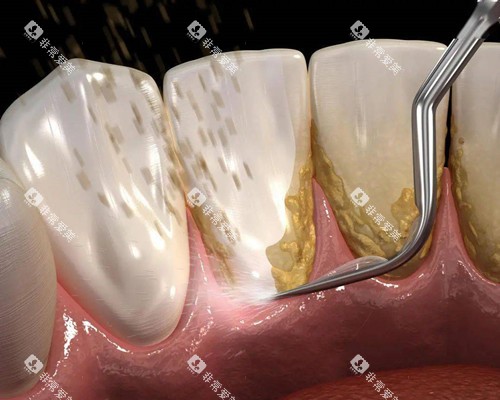

补牙是治疗龋齿等牙体疾病的常见方法。

该医院口腔科的补牙收费主要取决于补牙材料和龋洞的大小。

补牙材料

玻璃材料材料价格较为便宜,每颗牙齿的补牙费用在100 - 300元。

复合树脂材料美观度和耐磨性较好,是目前常用的补牙材料,费用在200 - 500元一颗。

银汞合金材料由于其含有汞等有害物质,现在使用相对较少,价格在150 - 300元一颗。

龋洞大小

浅龋和中龋的补牙相对简单,费用较低。

如果龋洞较深,接近牙髓,可能需要可靠行垫底等处理,费用会有所增加,大概会多收100 - 200元。